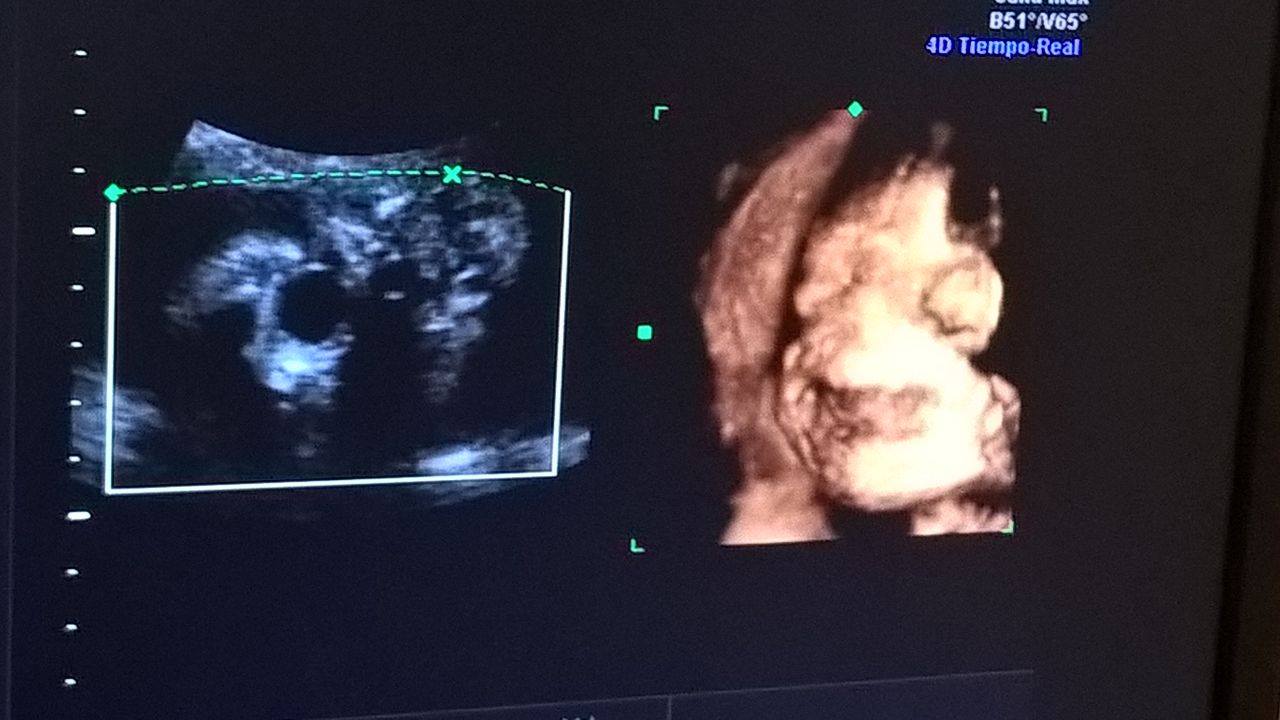

Les presento a Facundo Navil Arancibia

La verdad que es un sentimiento muy Hermoso el que me hace sentir esa foto

Despertó algo que nunca sentí

y les aseguro que no ay nada pero no ay nada comparado con la emocion y la Temocidad De querer tener a tu Hijo en tus brasos